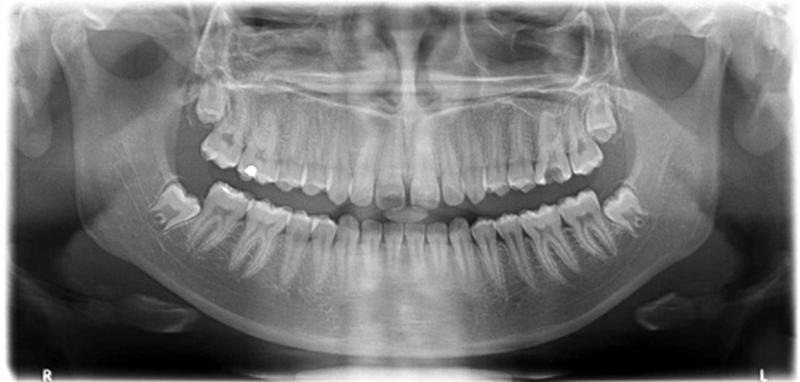

Panorámicas